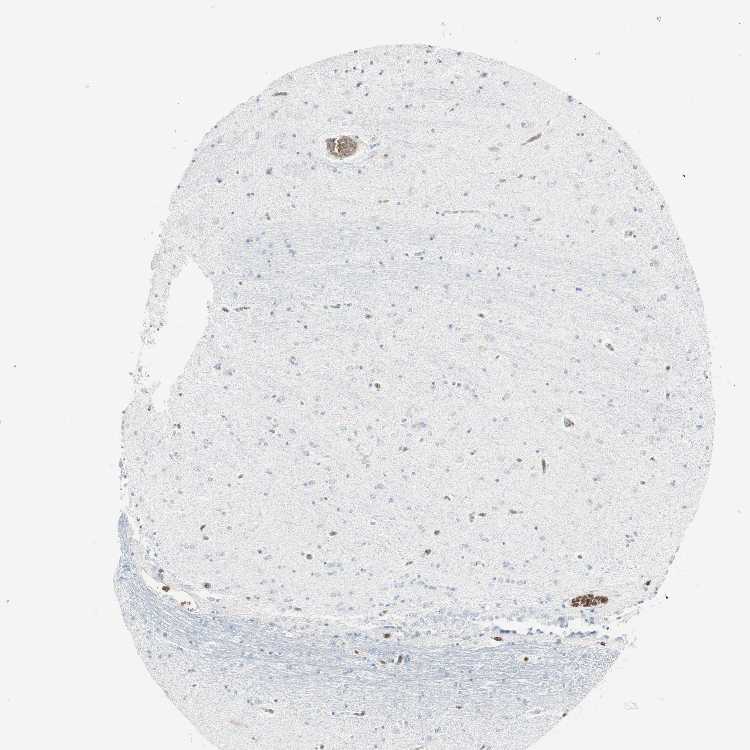

HIPPOCAMPUS - Antibody stainingi

Antibody staining in the annotated cell types in the current human tissue is reported as not detected, low, medium, or high, based on conventional immunohistochemistry profiling in selected tissues. This score is based on the combination of the staining intensity and fraction of stained cells.

Each image is clickable and will lead to virtual microscopy that enables deeper exploration of all samples and also displays staining intensity scores, fraction scores and subcellular localization as well as patient and tissue information for each sample.

Antibody HPA007419Antibody CAB007754

Glial cells Not detectedLow

Neuronal cells Not detectedLow